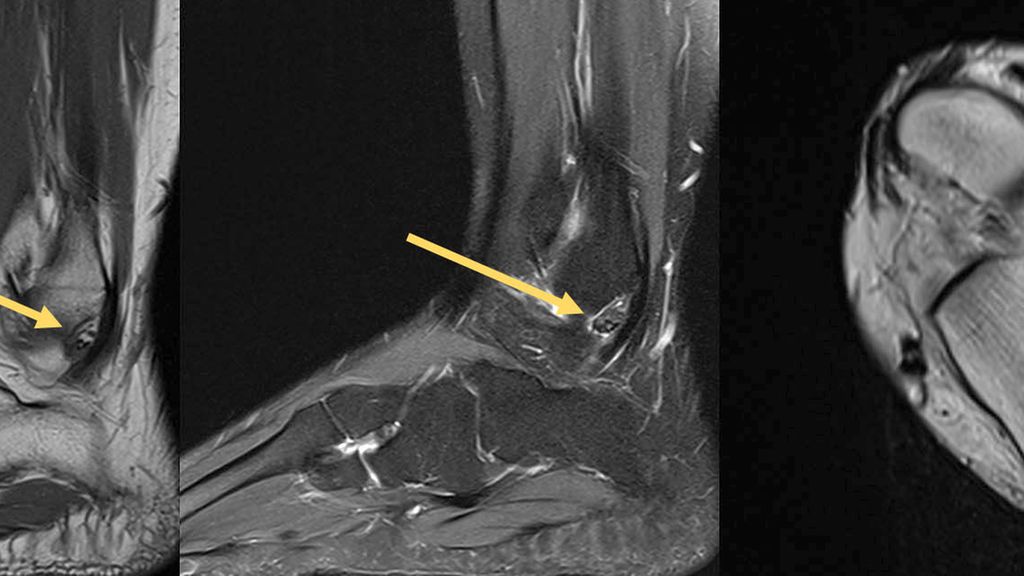

Der tenosynoviale Riesenzelltumor (TSRZT), welcher im deutschsprachigen Raum früher als PVNS (pigmentierte villonoduläre Synovitis) bezeichnet wurde, stellt wohl mit ca. 1,8 Neuerkrankungen pro 100000 Einwohnern pro Jahr die größte Gruppe an Läsionen dieser Art am Bewegungsapparat dar. Der Nomenklatur der WHO folgend soll der Terminus PVNS nicht mehr verwendet werden, da es sich histologisch um dieselbe Entität wie TSRZT handelt.6–9 Der TSRZT der Weichteile darf nicht mit dem des Knochens verwechselt werden. Der TSRZT kann ursächlich für synoviale Verdickungen und ein Überwachsen sein, wie in Abbildung 1 dargestellt. Normalerweise produziert die Synovia eine kleine Menge einer viskösen Flüssigkeit, welche die Gelenke bzw. den Knorpel „schmiert“ und so zu einem physiologischen Bewegungsablauf beiträgt. Der TSRZT produziert vermehrt diese Flüssigkeit, was Schwellung und Schmerz nach sich zieht. Oftmals wird dieser Zustand mit Erkrankungen aus dem rheumatoiden Formenkreis verwechselt. Im Falle des Vorliegens eines TSRZT ist die Dunkelziffer groß.8 Diese gutartigen Tumoren entstehen aus synovialem Gewebe: Gelenken, Sehnenscheiden oder Bursen. Große Unterschiede gibt es im lokalen Verhalten, man unterscheidet eine lokal aggressive (diffuse) von einer nodulären Wachstumsform (Abb. 2). Eine Metastasierung oder eine sarkomatöse Transformation sind extrem selten. Die diffuse Form wird von vielen als schwieriger in der Behandlung wahrgenommen, da sie destruktiver wächst und eine höhere Rezidivrate hat.10–12

Abb. 1: MRT eines tenosynovialen Riesenzelltumors (TSRZT) des Musculus tibialis posterior